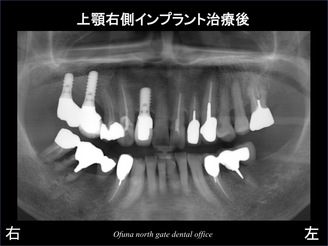

以下のレントゲン写真は上顎前歯部のインプラント治療が終了した状態です。

以下のレントゲンが治療終了後です。